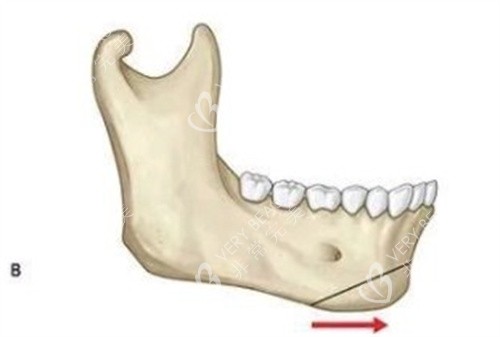

假体垫下巴:该方法是通过在下巴部位植入合适的假体材料来达到隆下巴的结果。假体通常有硅胶、膨体等,医生会在口腔内或下巴下方做切口,将假体放置到合适的位置,以增加下巴的长度和翘度。

假体垫下巴:适合只想对下巴进行微调,让下巴稍微变翘、变丰满的人群。对于下巴基础较好,只是希望有轻微改善的人来说,假体垫下巴是一个不错的选择。

假体垫下巴:术后能较快看到结果,下巴会明显变得更加翘挺。不过,假体在体内可能会随着时间出现一定的移位或老化等情况,需要定期进行检查。

假体垫下巴:可能会出现假体排异、移位、包膜挛缩等问题。不过,随着技术的发展,这些并发症的发生率已经有所降低。